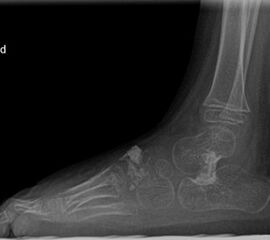

Röntgen Fuß AP und seitlich im Stand oder belastungssimuliert (Abb.1,2).

Röntgen seitlich in maximaler Plantarflexion bei Unklarheit über die Flexibilität.

Standaufnahme des oberen Sprunggelenkes: Bei Verdacht auf Instabilität oder Fehstellung des oberen Sprunggelenkes.